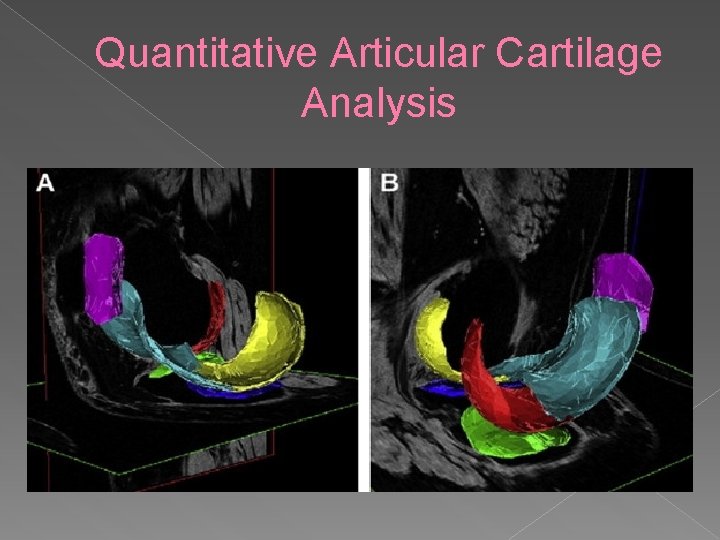

Quantitative Articular Cartilage Analysis High- resolution 3 D imaging sequences • Requires segmentation of the hyaline cartilage • Allows measure of tissue dimensions: • › › Cartilage Volume (VC) Cartilage Area (AC) Area of Subchondral Bone (t. AB) Area of denuded Subchondral Bone (d. AB)

Quantitative Articular Cartilage Analysis

Quantitative Articular Cartilage Analysis Interesting research tool • Quantitative nature makes it powerful • Found associations between: • › Weight gain and increased cartilage loss › Weight loss and decreased cartilage loss › High BMI/Leptin levels associated with cartilage loss › Systemic bone/subchondral bone density and risk of progression